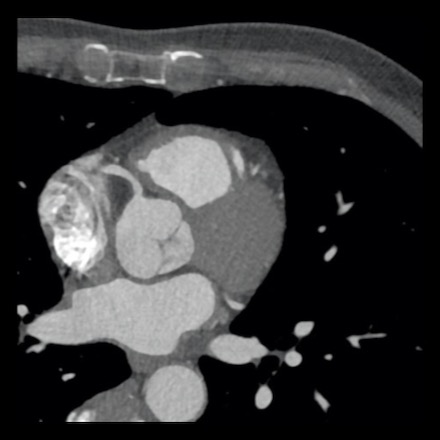

case 4 – CAD-RADS 3/P1/I+ thrombus left ventricle

First, scroll through the CTA images.

How would you describe the findings on the coronary CTA?

The findings are:

- Moderate (50-69%)

stenosis in the proximal LAD caused by a non-calcified plaque. - Variant of

sinoatrial (SA) nodal artery. The artery usually arises from the RCA as a second

branch after the conus artery, however in this case it arises from the LCX,

courses behind the aorta, anastomosing with the right atrium and with a small

branch supplies the SA-node of the heart. - Thrombus in the

apex of the left ventricle. - CTP was performed

in this patient. CTP showed a perfusion defect at stress imaging in the

territory of the LAD (I+), at rest no perfusion defect was visible.

This patient classifies as CAD-RADS 3/P1/I+, which means

this patient requires further investigation.